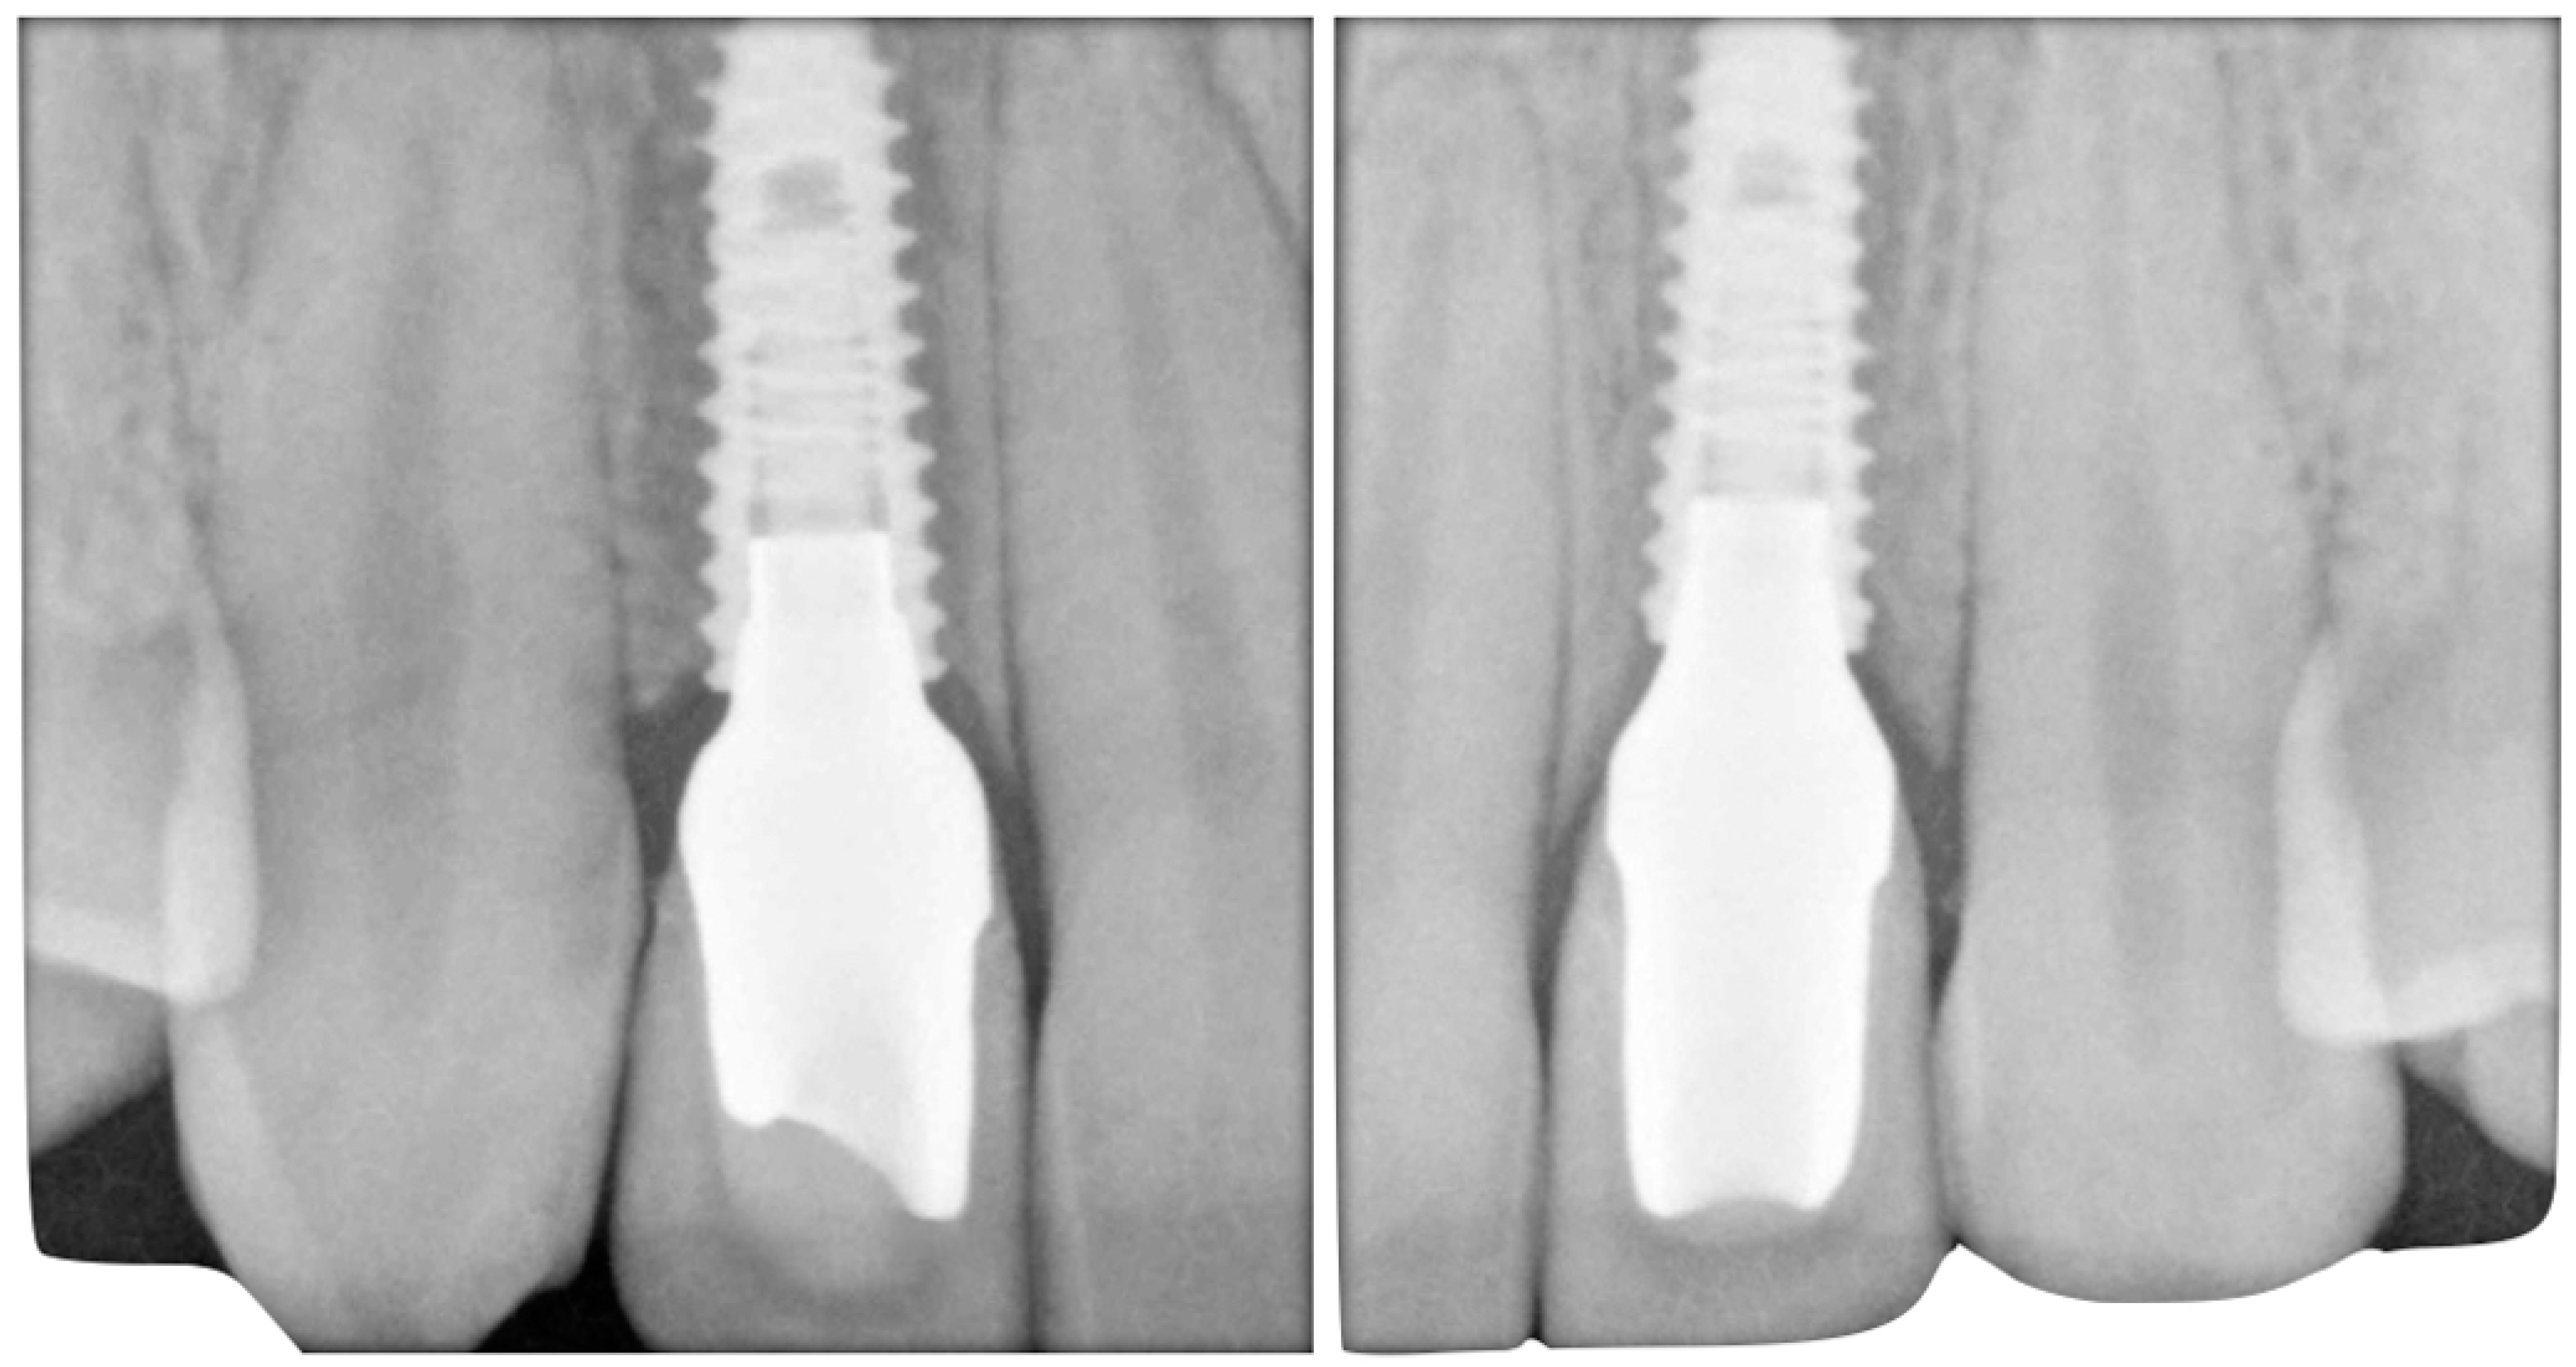

The case describes rehabilitating two congenitally missing lateral incisors in a young patient (38 years old) undergoing orthodontic treatment to create the necessary space for implant placement (Figure 1 and Figure 2). Two fibre-reinforced composite Maryland bridges (Tender Fiber Quattro—Micerium) were utilised for provisional rehabilitation (Figure 3, Figure 4 and Figure 5). Two Osstem TSIII 3.5 × 10.0 implants (1.5 mm subcrestal), two straight Osstem Zirconia abutments, and two-layered lithium disilicate crowns were employed for the definitive restoration (Figure 5, Figure 6, Figure 7, Figure 8, Figure 9, Figure 10, Figure 11, Figure 12, Figure 13, Figure 14, Figure 15, Figure 16, Figure 17, Figure 18, Figure 19 and Figure 20) [8,9]. The dental implant position was planned after a three-dimensional radiographic analysis in a prosthetically guided way. Patient rehabilitation was performed with an immediate post-surgery provisional (Maryland-type, cemented with a resinous cement) application. Subsequently, a delayed loading of the new provisional dental implant was retained (cemented with zinc oxide eugenol cement) and finally, definitive crowns (cemented with a definitive resinous cement) on Osstem® abutments were installed (3 months).

Initial models and diagnostic wax-ups were created using silicone (Elite HD+, Zhermack) with a closed tray technique, and provisional restorations were fabricated using different colours of acrylic resin (Jet Kit®, Lang, IL, USA). Temporary restorations were then placed in position (Figure 5). A transparent resin transfer key was employed to streamline the implant’s placement. The information regarding the implant’s position was conveyed to the laboratory through a series of specialized steps. These included the installation of titanium temporary abutments sourced from Osstem® in South Korea, securing the workpiece within the transfer key using pattern resin, precision drilling on the master hard stone model (Figure 6, Figure 7 and Figure 8), and an accurate placement of analogues in this model by employing a recasting technique with hard stone material (Figure 9). After revealing the implanted components, provisional restorations were promptly delivered as part of the uncovering procedure to encourage optimal soft tissue healing (Figure 10). Adjustments were made to the emergence profile to condition the surrounding soft tissues properly, and specialized conditioning procedures were carried out (Figure 11 and 12). Before and after conditioning, the changes in the profiles were documented (Figure 13). The new profiles obtained were transferred to the master model by mounting the modified provisional restorations with analogues, and a new artificial gum was created through recasting (Figure 14). Once the soft tissues had healed correctly, guided by the modified and polished provisional as in Figure 11, it was possible to transfer the mucosal profile onto the master model. By removing the provisionals from the oral cavity, they were then positioned on the master model, corresponding to the dental implant analogues in the master model. The master model that had previously been modified and freed from any over contours or undercuts was relined at this point with a laboratory silicone to simulate the profile of the mucosa. The abutments were customised using ceramic and fluorescence techniques to achieve optimal emergence profiles (Figure 15). Gingival profiles were assessed, and the abutments were inserted accordingly (Figure 16 and Figure 17). The final stage involved the placement of crowns, which were fabricated using ceramic material (E.max ceram®, Ivoclar, Naturno, Italy). A last radiographic check was performed to ensure a proper alignment and fit of the restorations. The case was considered completed, and aesthetic integration was achieved. Overall, this case report encompassed various steps, including an initial assessment, diagnostic procedures, provisional restorations, implant placement, emergence profile modifications, abutment customisation, crown placement, and the final evaluation of the completed case.

Figure 10. (a,b) Uncovering and delivering provisional restorations on implants with radiographical exam details. (c) Provisionals are delivered directly during uncovering for guided soft tissue healing.

Figure 18. Final bilateral radiographic check.

Prosthesis 05 00081 g018